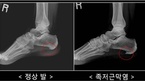

사무직에 종사하는 범모(36세, 서울시 노원구)씨는 최근 조깅을 시작했다. 가볍게 뛰다 보면 하루 종일 컴퓨터 앞에 앉아 일을 하면서 쌓인 피로가 말끔히 풀리는 기분이 들기 때문이다. 1주일 전, 여느 때와 마찬가지로 조깅을 나서려는데 발바닥에서 송곳으로 찌르는